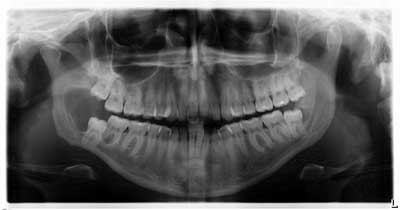

Our main concern was the extent of destruction—fracture potential and permanent paresthesia was extremely high. Following surgery, the patient was placed on a liquid diet for six to eight weeks. The specimen was sent to pathology. Diagnosis: dentigerous cyst. Follow-up over the course of the last year has proved to be promising—the bone has filled in, the patient has regained some feeling on the lower right side of her jaw and, thus far, there have been no recurrent or metastatic lesions observed. We are monitoring no. 17 and plan to remove it and the associated radiolucency when the bone has healed sufficiently in the right mandible.